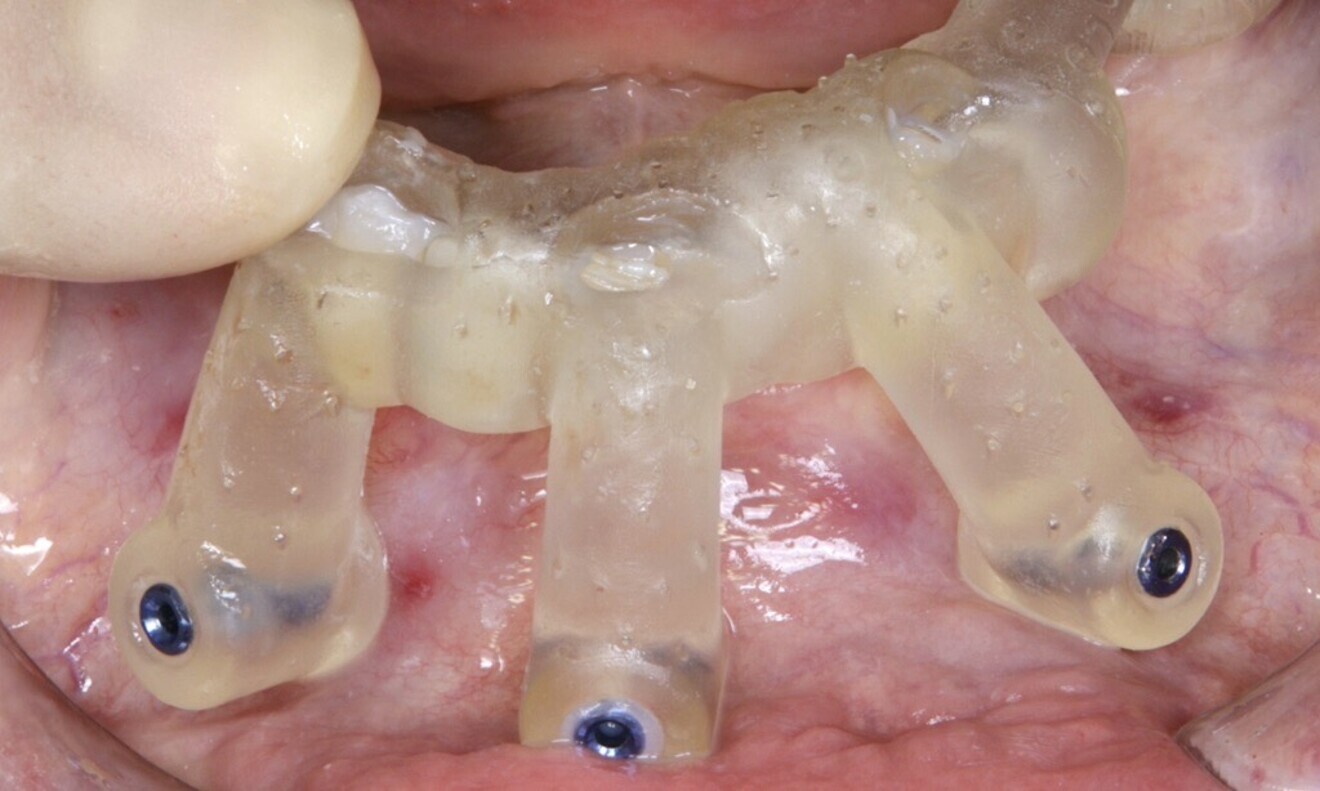

creation of a tooth- and mucosa-supported surgical guide to stabilise the drilling, ensuring accurate 3D positioning of the implants (22–28);

Figs. 16–28: The treatment workflow included the extraction of hopeless teeth, implant planning and positioning, and surgical guide fabrication.

For the mandibular arch, the first surgical guide was checked for proper fit (Fig. 29). The surgical guide, supported by the teeth, was placed, and anchor pins were inserted (Figs. 30 & 31). After this, the guide was removed, and the hopeless teeth were atraumatically extracted (Figs. 32 & 33).

The second surgical guide was placed, and bone and bone reduction was performed (Figs. 36–39). The third surgical guide was then placed for preparation of the implant bed, and the Straumann Surgical Cassette was used according to the pilot drilling protocol (Figs. 40–43). The implants were placed with the aid of the handpiece in a clockwise direction at a speed of 15 rpm and to a torque of 35 N cm (Fig. 44). Screw-retained abutments (Straumann) were placed according to the digital planning (Figs. 45 & 46).

As the implant loading protocol was immediate loading, after placement of the temporary copings, a restoration replica was adapted. In the laboratory, the analogues were placed (Figs. 47 & 48). Variobase abutments (Straumann) were placed on top of the screw-retained abutments to ensure stability and support of the provisional restoration (Figs. 49 & 50).